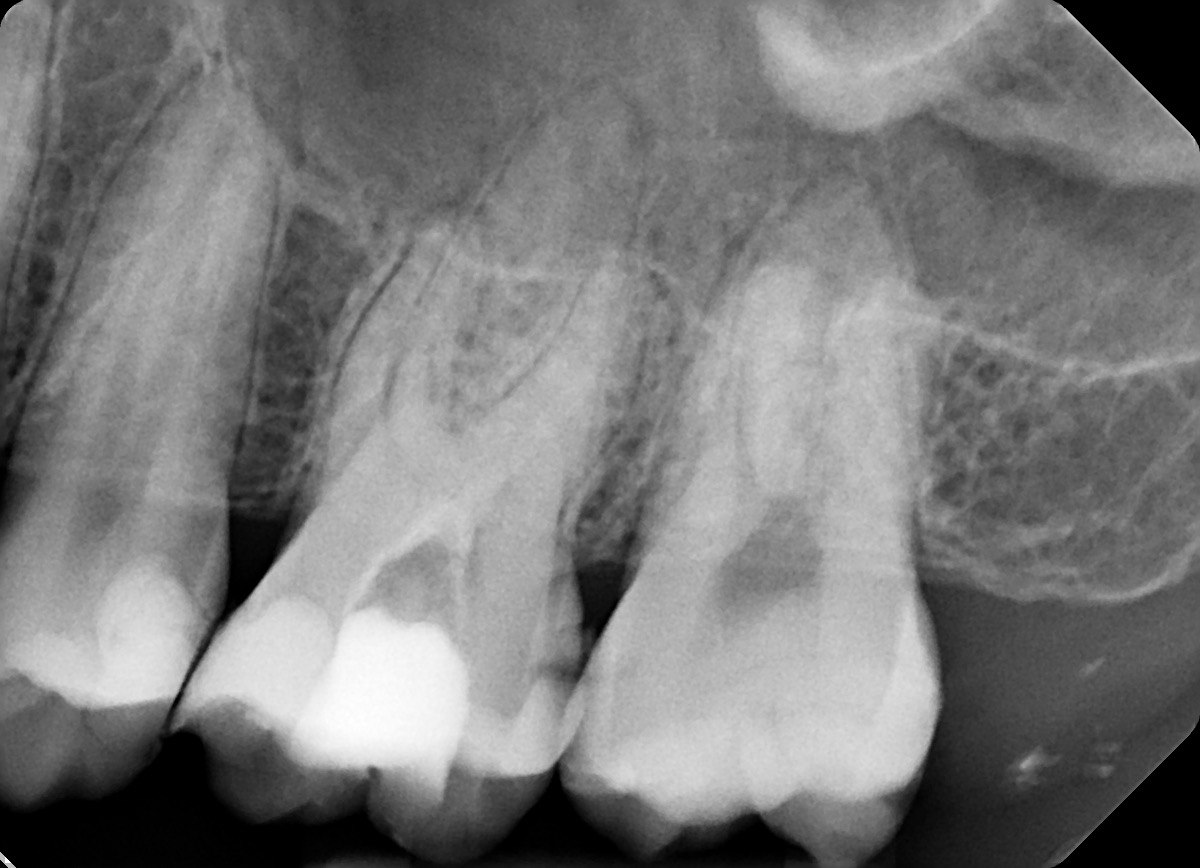

3. What surface require restoration?